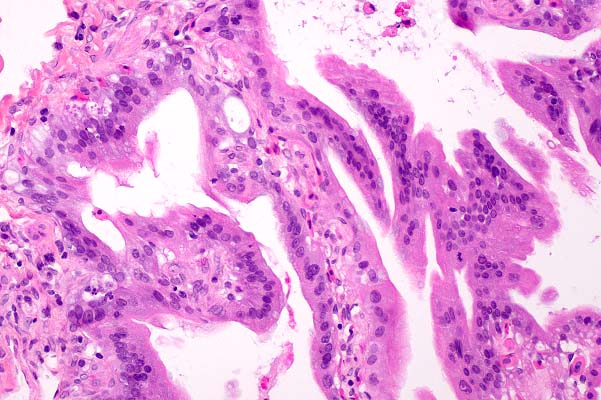

- Contributor's Diagnosis and Comments: Liver: granulomatous

hepatitis, multifocal, severe, with intralesional fungal hyphae

(Paecilomyces lilacinus)

40x

obj, PAS

- Case 29-3. Liver. Multiple branching septate fungal

hyphae are present within the lumen and the wall of a blood vessel.

-